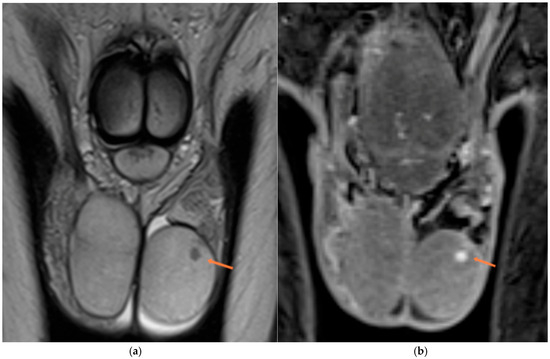

MRI of the Scrotum and Penis: Current Applications and Clinical Relevance

Background: Magnetic resonance imaging (MRI) plays an increasingly important role in the evaluation of scrotal and penile disorders, complementing ultrasonography in cases where findings are equivocal or complex. With its superior soft-tissue contrast, multiplanar capability, and advanced functional sequences, MRI provides unparalleled anatomic and tissue characterization across a wide range of male genital pathologies. Summary: This review summarizes current clinical applications of MRI in scrotal and penile imaging and discusses its diagnostic value, protocol optimization, and interpretive features. In scrotal pathology, MRI accurately differentiates torsion, trauma, infection, and neoplasms, aiding in the distinction between benign and malignant testicular lesions and supporting testis-sparing management. Quantitative diffusion and perfusion metrics further refine lesion characterization. In andrology, MRI biomarkers such as apparent diffusion coefficient (ADC), magnetization transfer ratio (MTR), and proton spectroscopy serve as promising non-invasive indicators of spermatogenic activity in male infertility. In penile imaging, MRI enables precise local staging of carcinoma, assessment of plaque morphology and activity in Peyronie’s disease, evaluation of tissue viability in priapism, and detection of prosthesis-related complications. Conclusions: MRI has become an essential problem-solving tool in the assessment of scrotal and penile diseases, enhancing diagnostic confidence and surgical planning. Future directions include protocol standardization, quantitative parameter validation, and the integration of radiomics and artificial intelligence to improve reproducibility and clinical impact. Full article

Figure 1